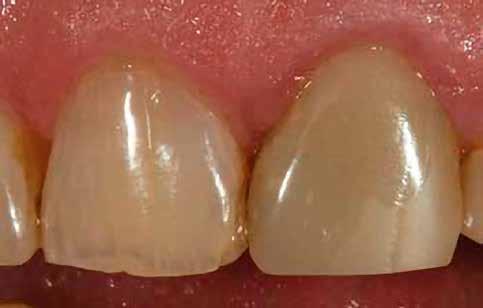

Egy 30 éves, negatív kórtörténettel rendelkező beteg azzal a kéréssel fordult hozzánk, hogy cseréljük ki az UR1 traumája után, 10 évvel korábban készült korábbi kompozit-helyreállítást.

A klinikai vizsgálat során az UR1 reagál a viabilitási tesztre, és az ugyanazon a napon készült röntgenfelvételen nem mutat periapikális elváltozásokat (1. ábra).

Az UR1 elszíneződött, és palatálisabb helyzetben van, mint az ellenoldali központi UL1 (2. ábra)

A pácienst 21 nap (14–15. ábrák) és 12 hónap (16. ábra) után ismét ellenőrizzük, hogy értékeljük az esztétikai eredményt a forma és a szín tekintetében.

13. ábra: Az UL1 emulálása polírozás közben. – 14. ábra: A helyreállítás 21 nap után.

15. ábra: A helyreállítás 21 nap után.

16. ábra: A helyreállítás 12 hónap után.